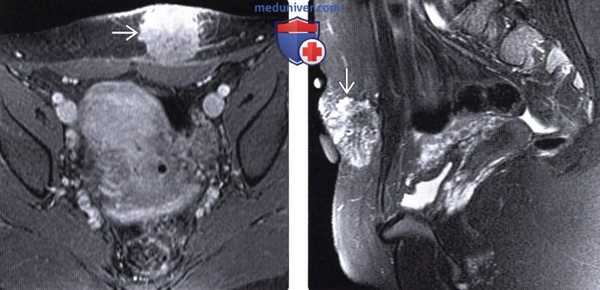

(Слева) На аксиальной КТ с контрастным усилением у молодой женщины с кесаревым сечением в анамнезе и циклическими боля ми в передней стенке таза определяется образование с лучистыми краями в передней стенке таза с левой стороны.

(Справа) На аксиальной Т1 МР томограмме с контрастным усилением у этой же пациентки определяется объемное образование, активно накапливающее контраст. Локализация образования соотносится с расположением рубца после кесарева сечения. На операции была подтверждена эндометриома брюшной стенки.

(Слева) На аксиальной Т1 МР томограмме с контрастным усилением у молодой женщины с жа -лобами на боль в области рубца после кесарева сечения определяется объемное образование, активно накапливающее контраст, которое является эндометриомой брюшной стенки.

(Справа) На сагиттальной Т2 МР томограмме у этой же пациентки визуализируется очаг поражения, гиперинтенсивный на Т2-ВИ, гипоинтенсивный на Т2 ВИ (изображение не представлено). Эндометриоз брюшной стенки выглядит не так, как типичный эндометриоз: для него характерны гипоин-тенсивный сигнал на Т1 и гиперинтенсивный на Т2, а также умеренно выраженное контрастное усиление.